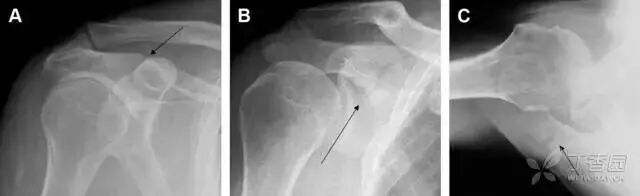

23单纯肱骨大结节骨折

与其它肱骨近端骨折不同,单纯肱骨大结节骨折常发生于年轻人。肱骨大结节骨折常由撞击或剪切/撕脱损伤所致:

撞击包括直接撞击、肩峰撞击、上关节盂撞击(极度外展时);

剪切/撕脱损伤常发生于肩关节前脱位。

在常规前后位片上,大结节与肱骨头重叠,骨折不易发现,外旋位前后位片有助于诊断。

图 1 大结节骨折。(A)脂肪抑制序列斜冠状位 MRI,显示肱骨大结节线性骨折无移位(箭头)与周围骨水肿;(B)外旋位前后位(AP)片,证实大结节骨折(箭头),典型的骨折愈合过程中的骨吸收表现;(C、D)初诊时内旋位、外旋位前后位片,初诊时漏诊,仔细回顾影像,内旋伞下可见双密度影(椭圆),骨皮质中断(箭头)